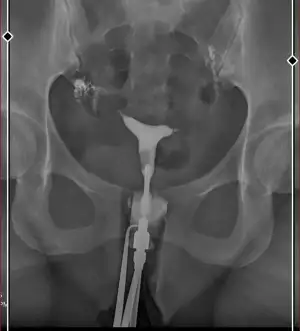

Kızlar bugün rahim filmi çektirdim doktor çok şükür hiçbir sorun yok kanlar tüpler rahim olması gerektiği gibi dedi, ama benim tüplerim bi değişik geldi bana ggoogleden bakıp karşılaştırdığım da özellikle bir taraf çok yukarda gibi düşüncelerinizi söyler misiniz ?

yapısı öyle o sorun değil , sıvı da batına dağılmış açık tüpler sorun yok bence

Sorun yok insan vücudunda iki taraflı olan şeylerde biri birinden farklı olabiliyor tüpler tıkalı olsa hiç çıkmaz boyama hiç olmaz endişe etme

Yok askm hiçbirşey demedi bende eve geldiğimde bakınca fark ettim acaba verilen sıvı orada birikmiş olabilir mi diye düşündüm aletin ucunda tıpa gibi birşey varmış sıvının geri gelmemesi için, başka bir şey olsaydı söylerdi diye düşünüyorum

Chate sor kuzucum ☺️ tek bi görüntüye bakılarak sorun var demek olmaz diyecektir. Doktorlar bunu tek görsele bakarak demiyor boyama yaparken perde vs herşeyi en ince ayrıntısına kadar bakıyor bende de sol da sağda ki kadar ileri gitmemişti endişe etmiştim raporum gelince düzgün olduğunu anlamıştım endişe etme

Benim rahim filmime benziyor doktor bana polip var dedi hitereskopi olmam gerekiyor

Ama sonuçta böyle büyük bir polip olsaydı sizcede bunu söylemez miydi, ve bildiğim kadarıyla polip rahmin iç daha iç kısmında oluyor geçen yıl ameliyatını olmuştum

Aynen askm zaten bildiğim kadarıyla polip daha yukarda orta kısımda oluyor geçen yıl bunun için ameliyat oldum zaten böyle birşey olsa doktor illaki görür ve söyler diye düşünüyorum